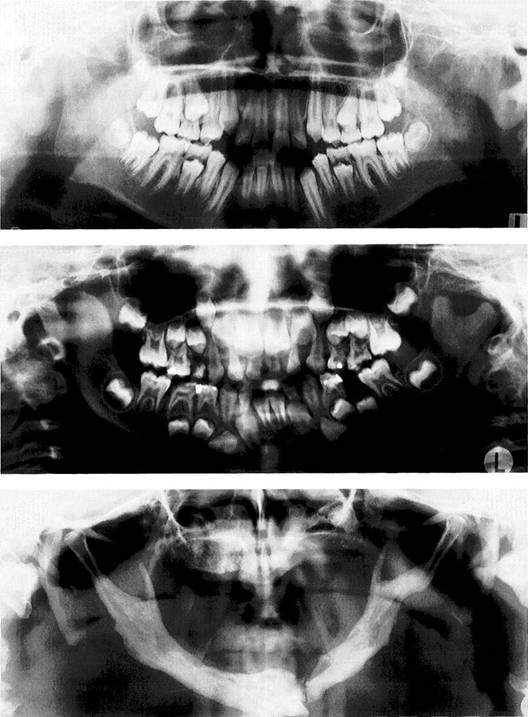

Juvenile chronic arthritis

Panoramic radiograph of a 10-year-old with chronic juvenile arthritis. Approximately 10% of children with this disease and near normal forma­tion of the facial bones exhibit de­generative changes in the condyles (Pearson and Ronning 1996). In pa­tients with severe skeletal changes ("bird-face retrognathism") the condyles always show advanced re­sorption. Early functional treat­ment can improve the skeletal problems (Pedersen et al. 1995, Paulsen 1997).

Goldenhar syndrome

Panoramic radiograph of a 6-year-old with Goldenhar syndrome (oculoauriculovertebral dysplasia). While the right ascending ramus and condyle have developed nor­mally, on the left side there is un­derdevelopment and shortening of the condylar process. In patients with syndromes, the extent of involvement of the temporo­mandibular joint is of special inter­est because this determines the type of treatment (functional jaw orthopedics, Herbst hinge appli­ance, distraction osteogenesis, re­constructive dentistry).

Pyknodysostosis

A 56-year-old man with a sponta­neous fracture of the mandible associated with pyknodysostosis. Pyknodysostosis is a rare form of sclerosing osseous dysplasia with an autosomal recessive inheritance (Maroteaux and Lamy 1962, Kark-abi 1993)..The temporomandibular joints themselves are usually not affected (Yamada et al. 1973, Zachariades and Koundouris 1984), but the osteomyelitis that fre­quently accompanies it can some­times mimic a temporomandibular joint problem (Iwu 1991, Schmitzet al. 1996).